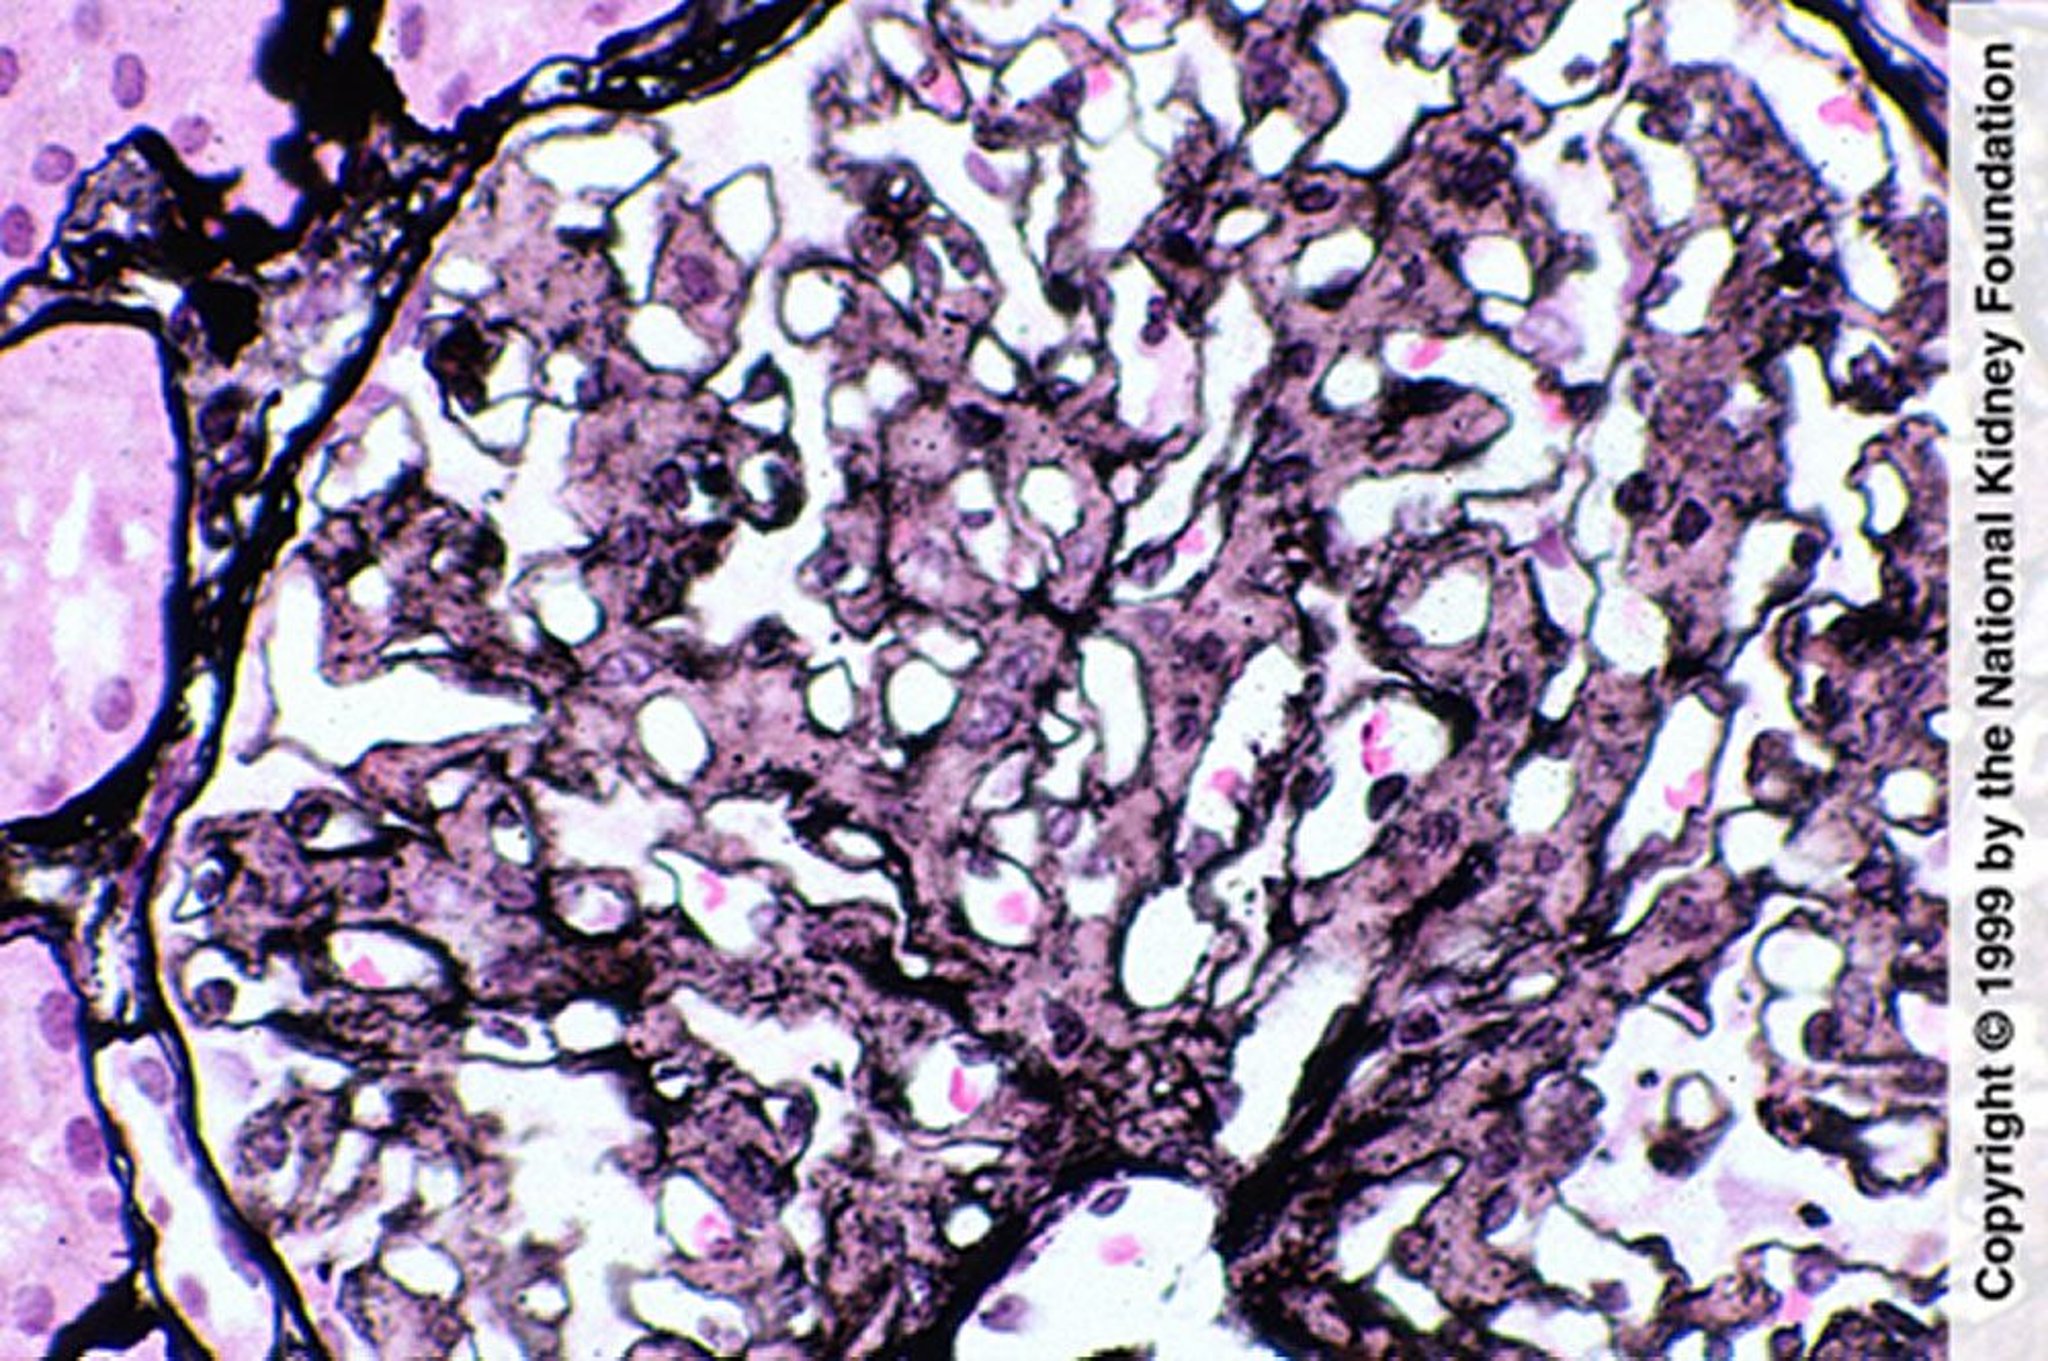

Glomérulopathie fibrillaire (prolifération mésangiale)

La prolifération mésangiale est évocatrice de glomérulopathie fibrillaire; cependant, le diagnostic nécessite une coloration négative au rouge Congo, une coloration IgG par immunofluorescence et la mise en évidence de fibrilles au microscope électronique (coloration de Jones à l'argent, ×400).

Image fournie par Agnes Fogo, MD, and the American Journal of Kidney Diseases' Atlas of Renal Pathology (voir www.ajkd.org).